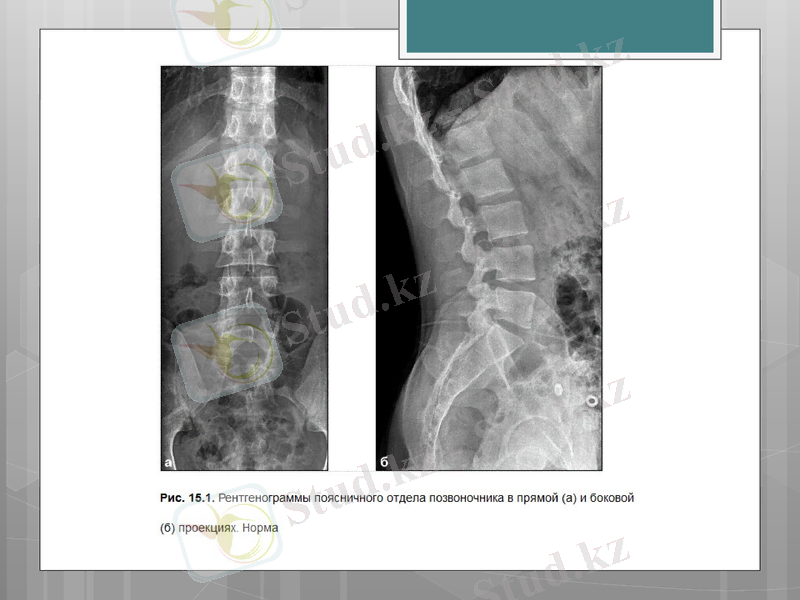

Омыртқаның бел-сегізкөз бөлімінің рентгенологиялық зерттеуінде анатомиялық ерекшеліктері бар.

Тура кескіндегі спондилограмма бел омыртқаларының пішінін, жиегін және құрылымын, омыртқааралық дисктердің биіктігі мен пішінін, омыртқа статикасының ерекшілігін зерттеуге мүмкіндік береді.

Бүйір суретте омыртқаның денелері және омыртқааралық дисктер жақсы көрінеді, жабылатын пластинкалар мен доғаның аяқшалары айқын көрінеді. Омыртқааралық дисктер де жақсы көрінеді. Бүйір суреттер омыртқа денелерінің биіктігінің біркелкілігі және омыртқааралық дисктердің жағдайы туралы дұрыс бағалауға мүмкіндік береді. Бүйір спондилограмма осы омыртқа бөлімінің даму ауытқуы, дегенеративті-дистрофиялық, қабыну, ісікті аурулар және жарақаттық зақымданулардың диагностикасы үшін маңызды ақпарат береді.